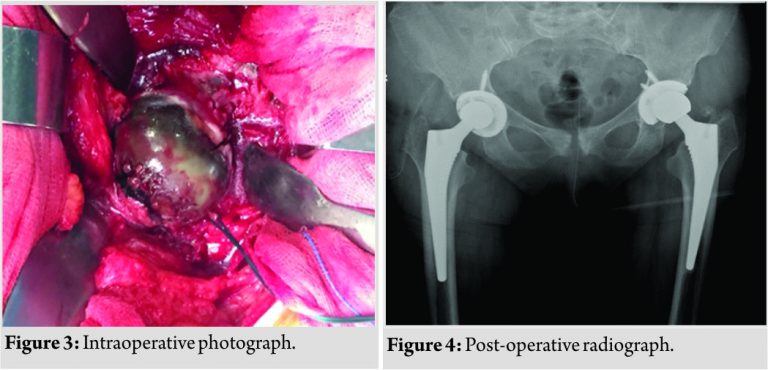

Magnetic resonance imaging of the hips confirmed the same. The authors decided to proceed with a total hip replacement of both her hips. The goal of surgery was to obtain a painless range of motion for both her hips. A staged bilateral total hip replacement surgery was performed9months apart. The anterolateral approach was the preferred approach used by the treating author. Intraoperatively, the head of the femur presented a blackish-brown discoloration, and the surrounding tissues had a brownish tinge to them (Fig. 3).

Special care was taken to remove as much of the capsule as possible to prevent local recurrence. The Corail Pinnacle poly on the metal implant with head size 32+1.5, stem size 11, and acetabulum cup size 50 was used for the left hip. The Corail Pinnacle poly on metal implant with head size 28+1.5, stem size 12, and acetabulum cup size 50 was used for the right hip. The post-operative period was uneventful (Fig. 4). The patient was made to ambulate within 3 days of surgery. The patient was initiated on a planned physiotherapy program. Our patient regained functional range of movements by the end of 3 months. The patient was independently ambulant and pain free with no complaints at the 1½-year follow-up.